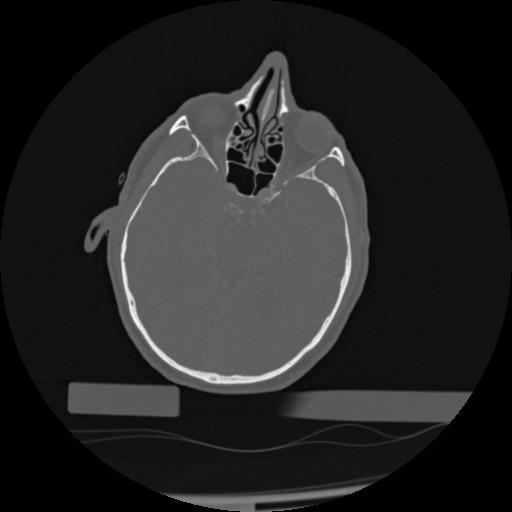

22 ANGIO,CE,Vol,0.5,ANGIO,,